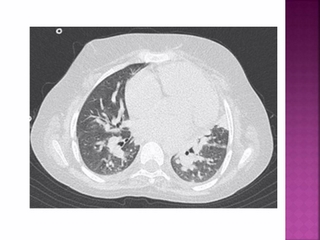

فوق تخصص رادیولوژی اطفال

دکتر رکسانا آزما